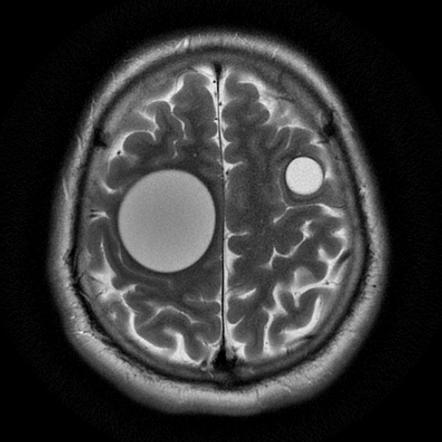

На Т2-взвешенных изображениях выявляется гиперинтенсивное жидкостное образование с равномерным сигналом и тонким гипоинтенсивным ободком, отражающим фиброзную капсулу.

Внутри основной кисты выявляются множественные дочерние кисты с типичной многоуровневой структурой, гипоинтенсивные на Т1-взвешенных изображениях и гиперинтенсивные на Т2-взвешенных изображениях.

При крупных образованиях выявляется выраженный масс-эффект в виде смещения срединных структур, компрессии желудочковой системы и признаков внутричерепной гипертензии.